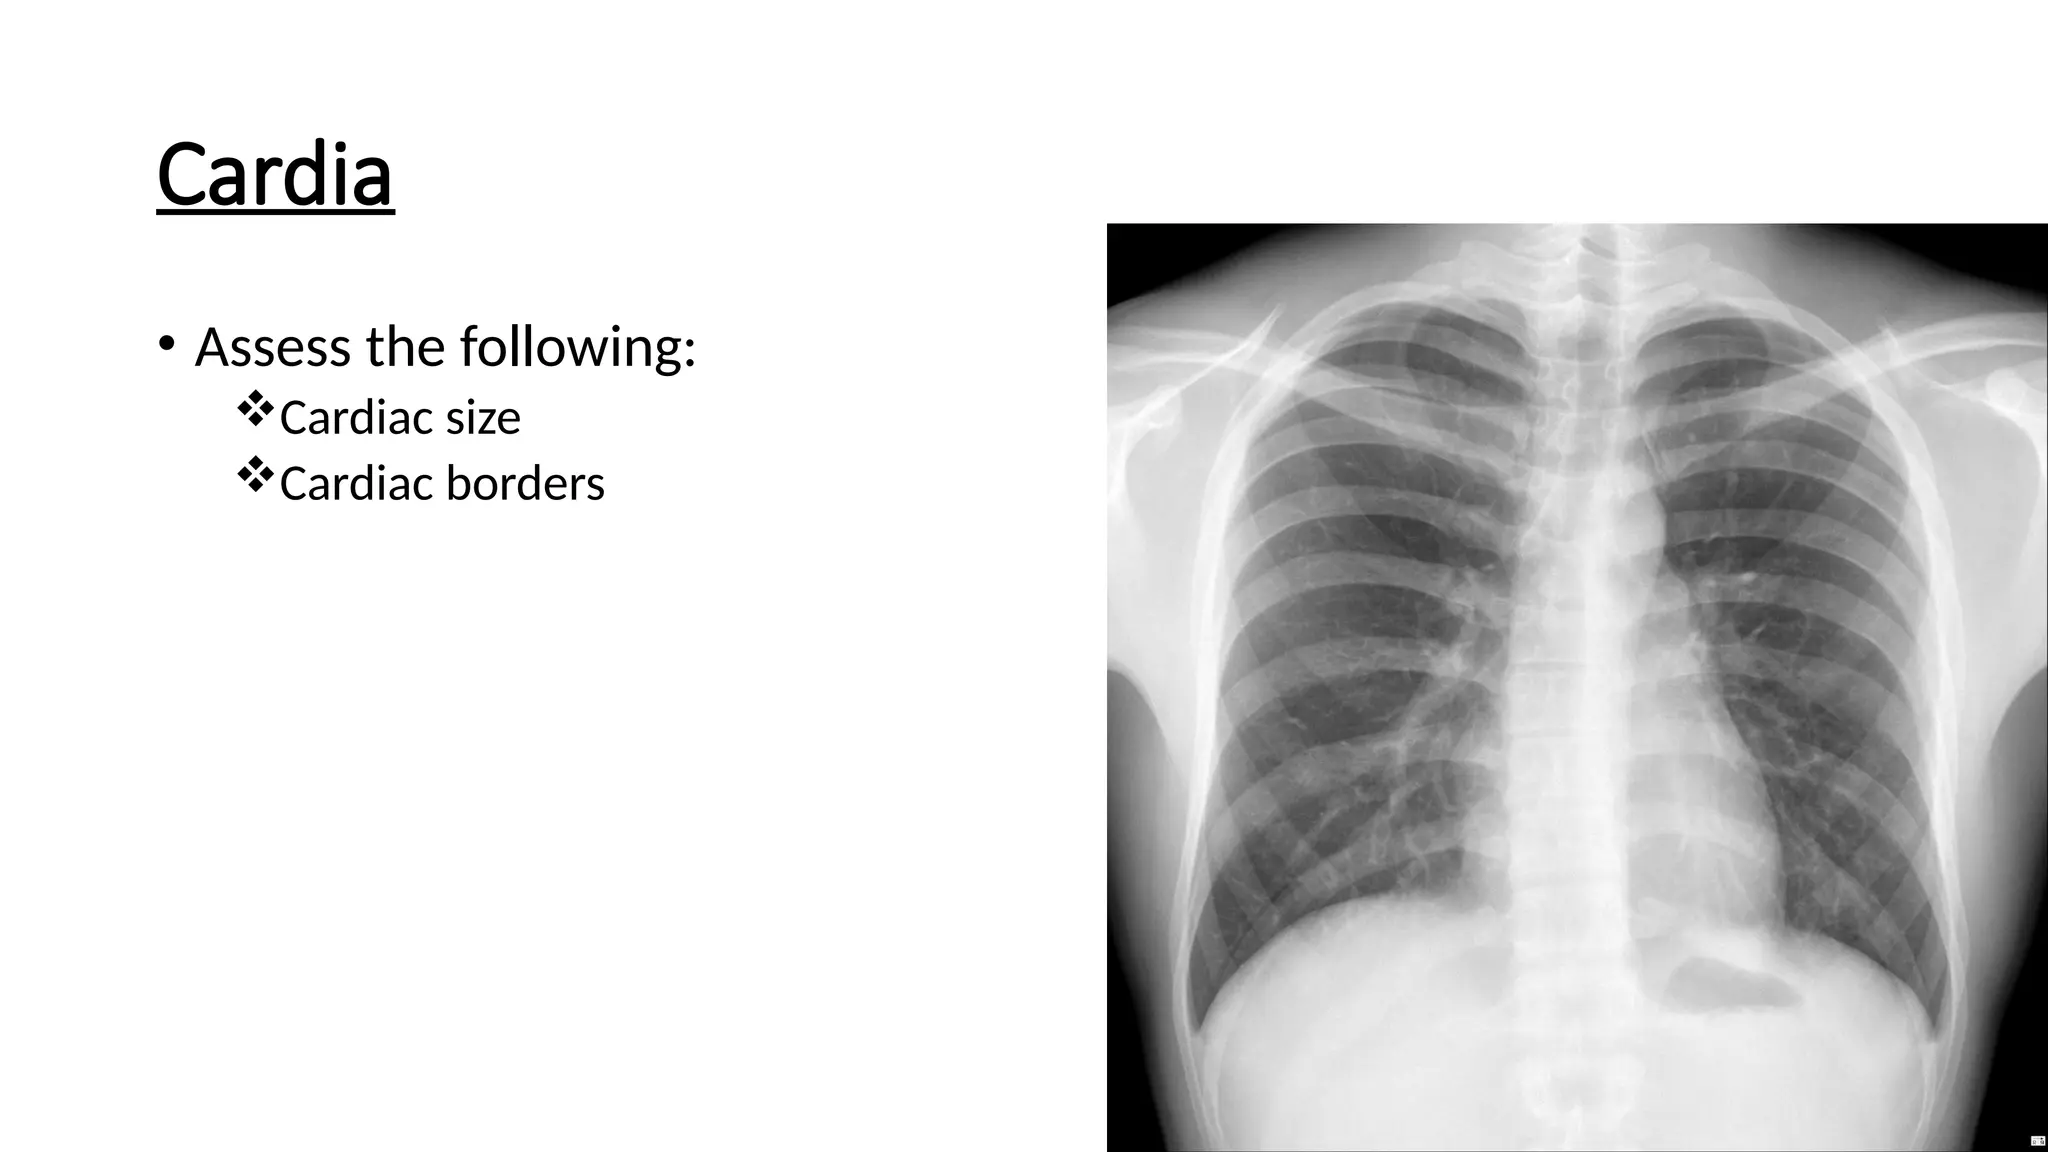

Cardia

• Assess the following:

Cardiac size

Cardiac borders

Cardiac size

• Normal <50% of the thoracic

window

• >50% of thoracic window

Cardiomegaly

Accurate assessment requires PA chest x-ray

As AP films exaggerate the size of the heart